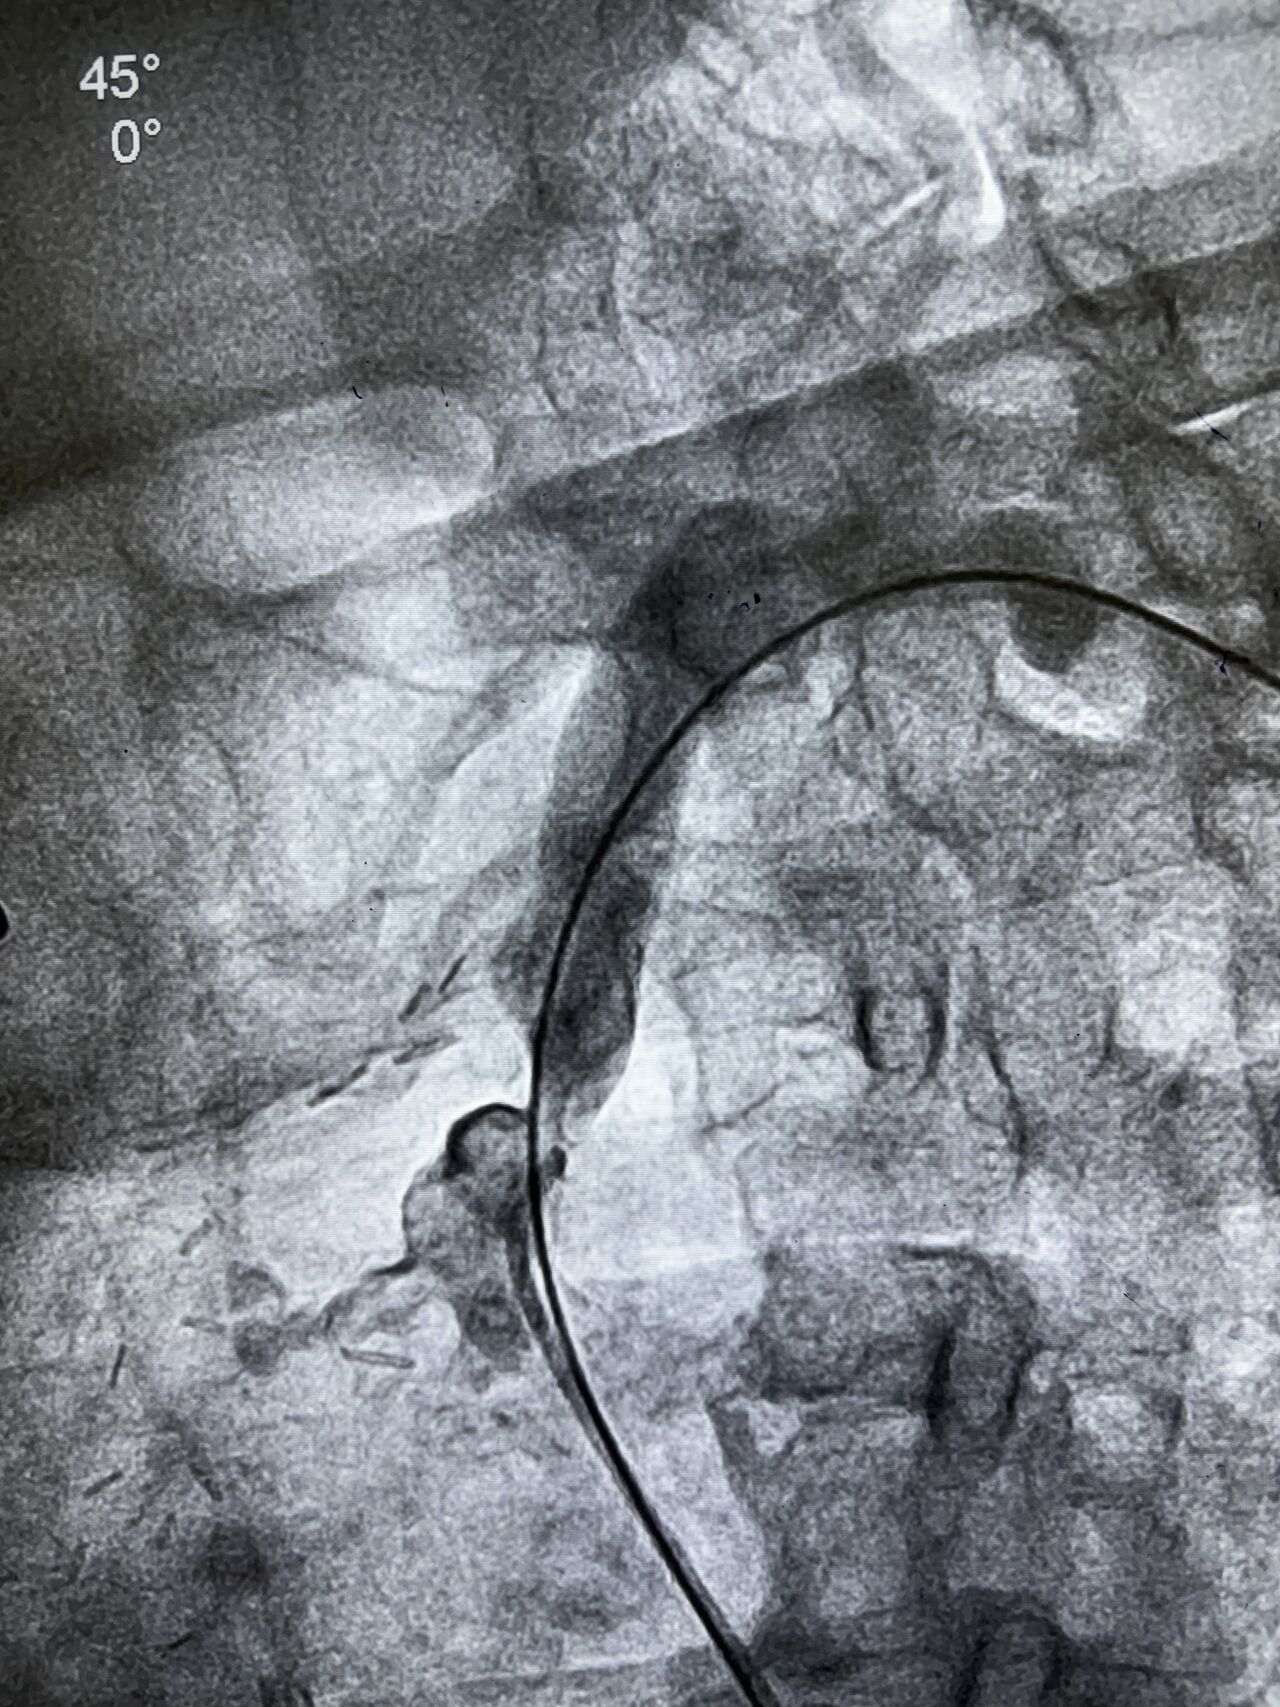

Beyond Patent Grafts: Expert Management of Incidental Subclavian Artery Obstruction in a Post-CABG Patient

Another Interesting Case Incidental Left Subclavian Obstruction During LIMA Cannulation Managed with Peripheral Intervention ```…